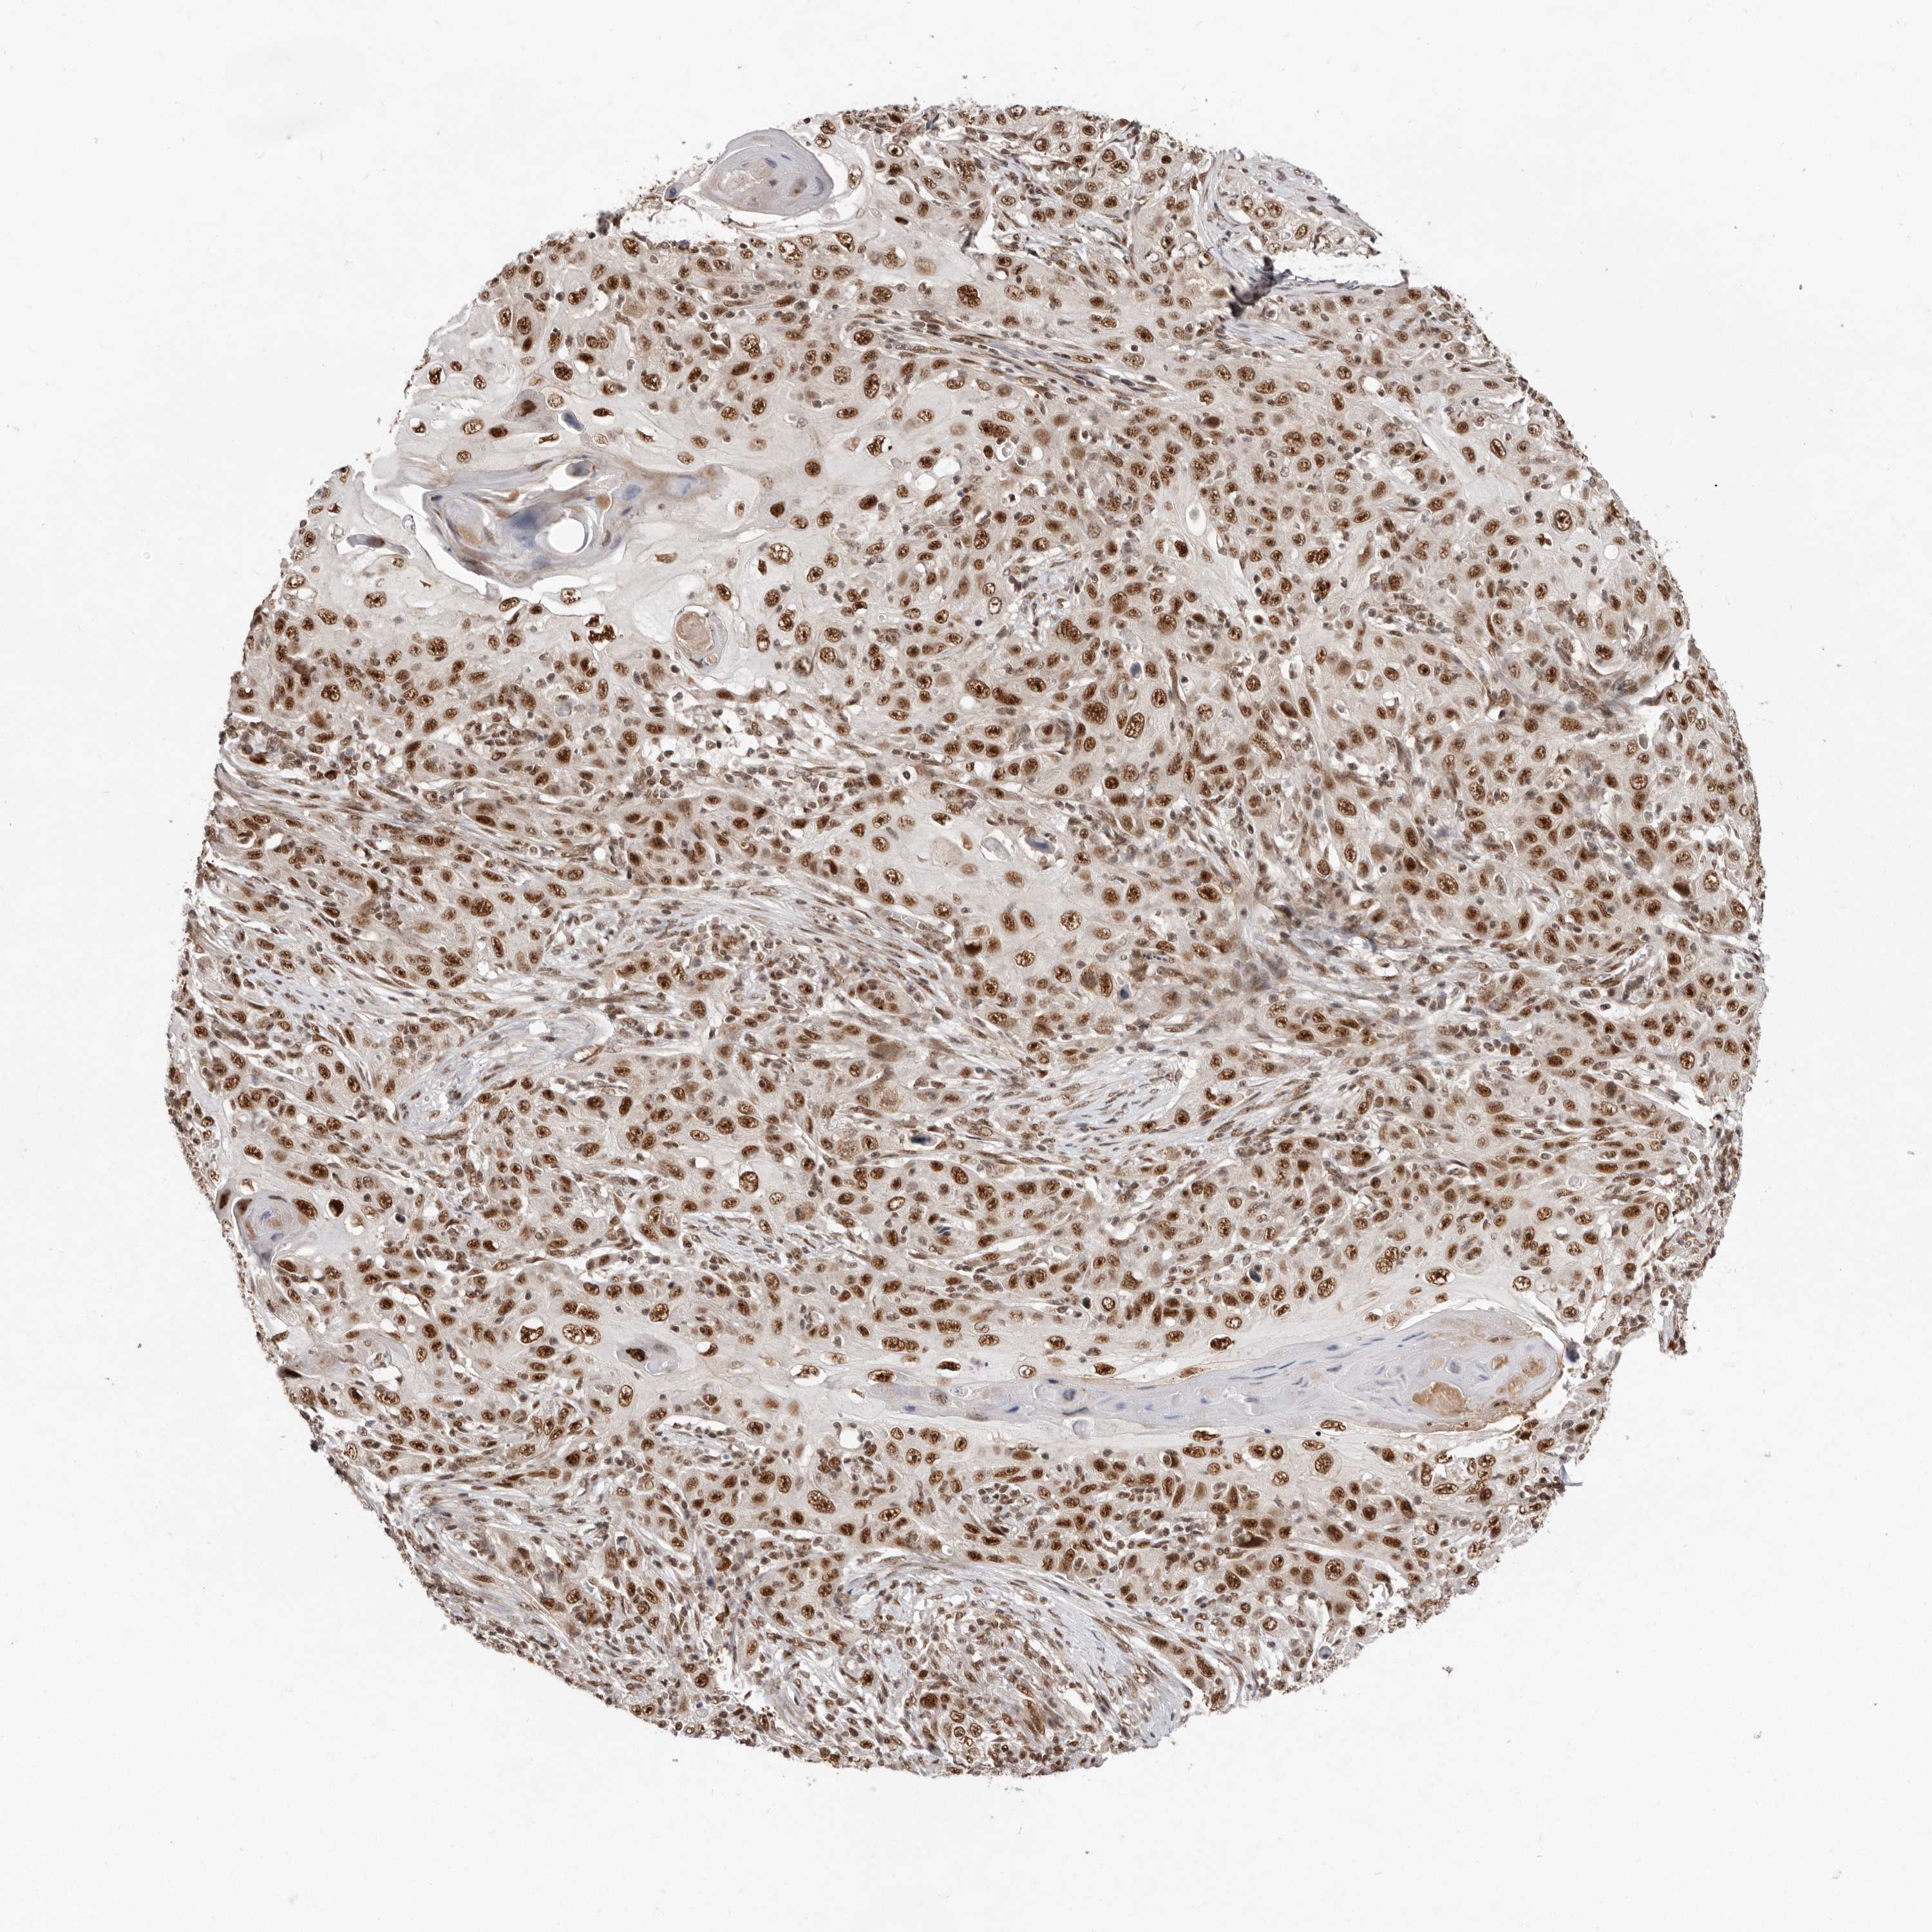

Antibody HPA028647

Staining

High

Intensity

Strong

Quantity

>75%

Location

Nuclear

Basal cell carcinoma